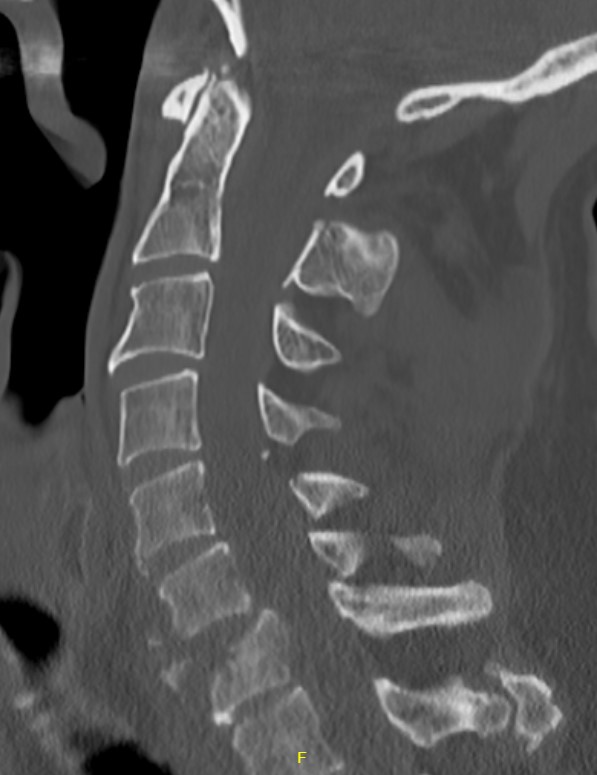

CT

Injury to anterior and middle columns, with retropulsion +/- posterior column

Pathology

Anterior & middle columns fail

- if severe, posterior ligament complex fails

Canal compromise / neurological injury

- retropulsed fragments

- typically one or two main retropulsed fragments